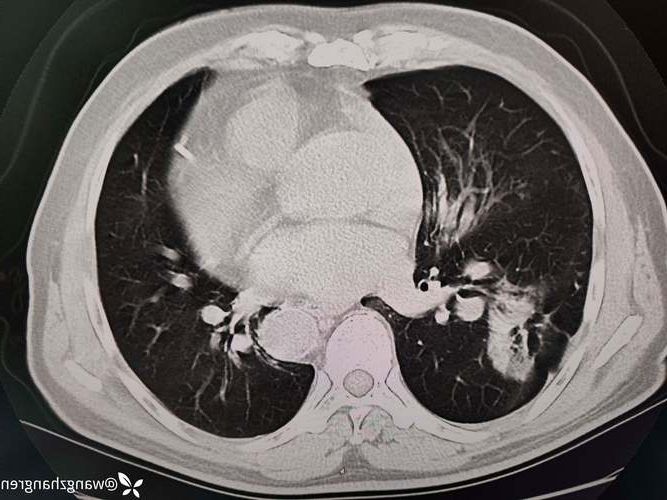

8月25日,九寨沟县在常态化核酸检测中发现1例无症状感染者,目前相关应急处置工作已全面展开。

该感染者系省外返县人员,在“入川即检”闭环管理中发现,已第一时间转运至定点医院隔离医学观察。其相关活动轨迹已公布,密接、次密接人员均已落实管控,首次核酸检测结果均为阴性。